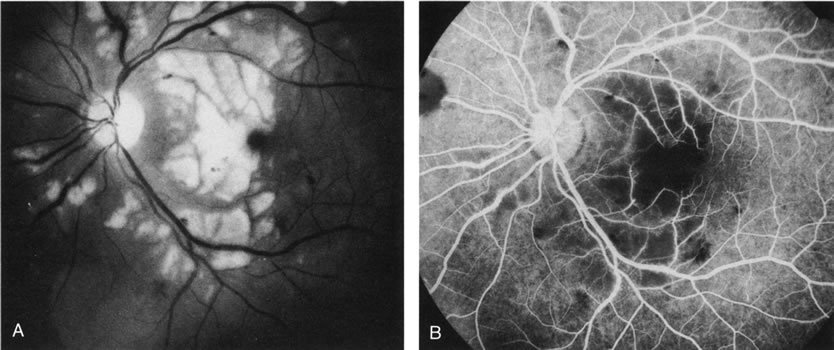

Fig. 5. A. Clinical photograph of a large, crescent-shaped rip of the retinal pigment epithelium (RPE) in the temporal macula. B. Early-phase fluorescein angiography study demonstrates the presence of a window defect corresponding to the RPE rip, which exposes the choroidal vasculature. Where the RPE is redundant in the central macula there is blockage of the normal choriocapillaris fluorescence. C. Late-phase angiogram reveals intense hyperfluorescence seen through the RPE defect.